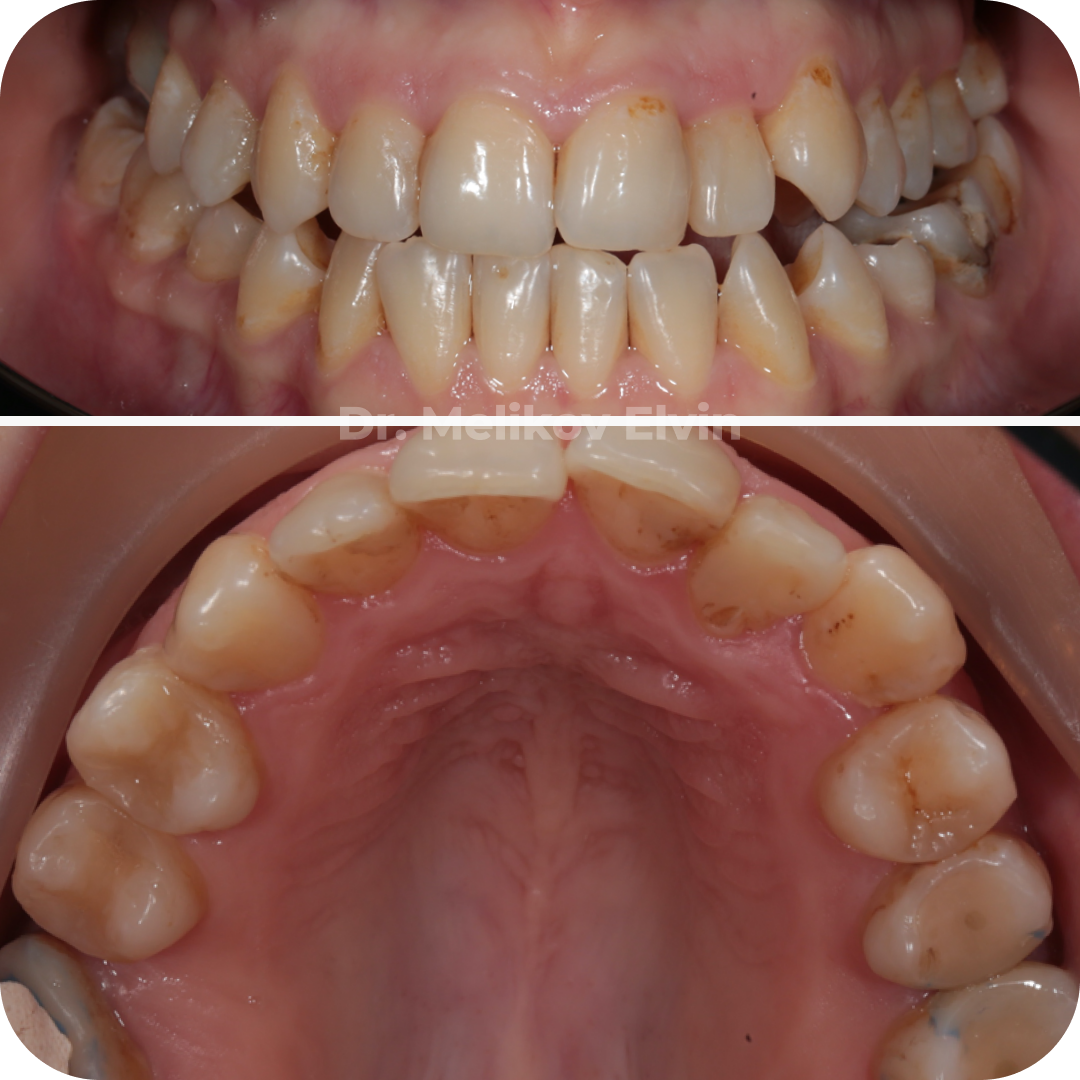

Фотографии до операции по расширению верхней челюсти.

На этапе ортодонтического лечения:

Закрытие диастемы и нормализация зубных рядов